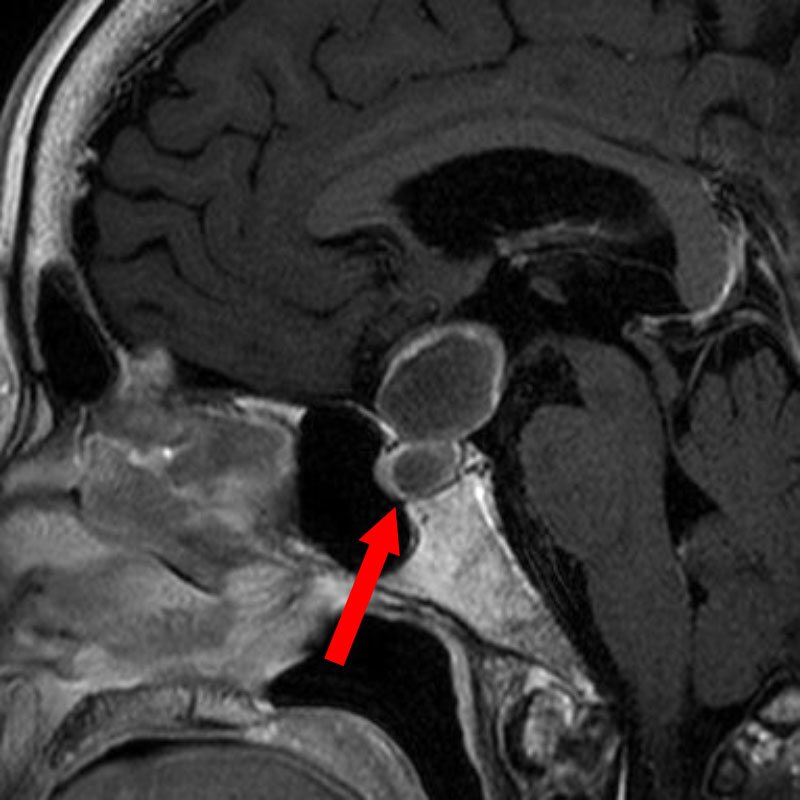

694

'25年11月

90代

頭蓋咽頭腫

頭蓋内腫瘍摘出術

No.’25_96 手術前1

No.’25_96 手術前2